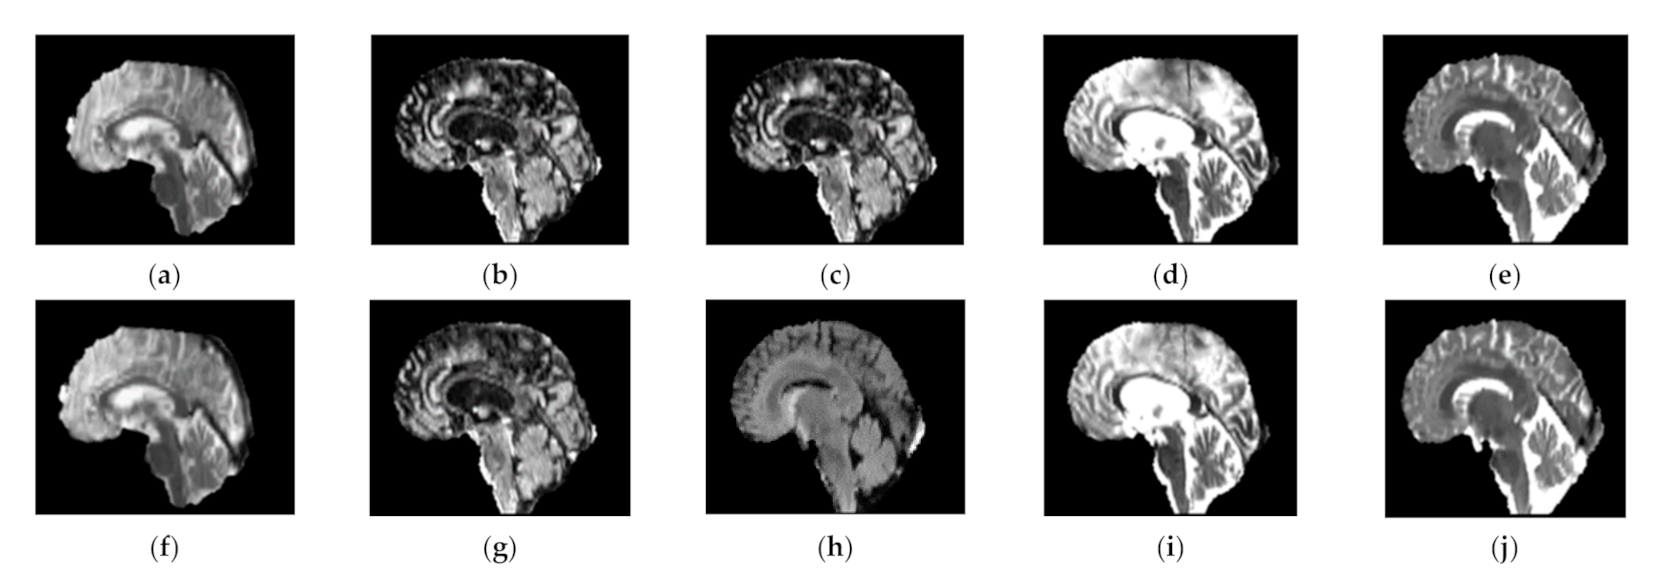

3.2. Utilized Pre-Processing Techniques

3.2.3. Histogram Equalization

3.2.4. Gibbs Ringing Artifact Removal